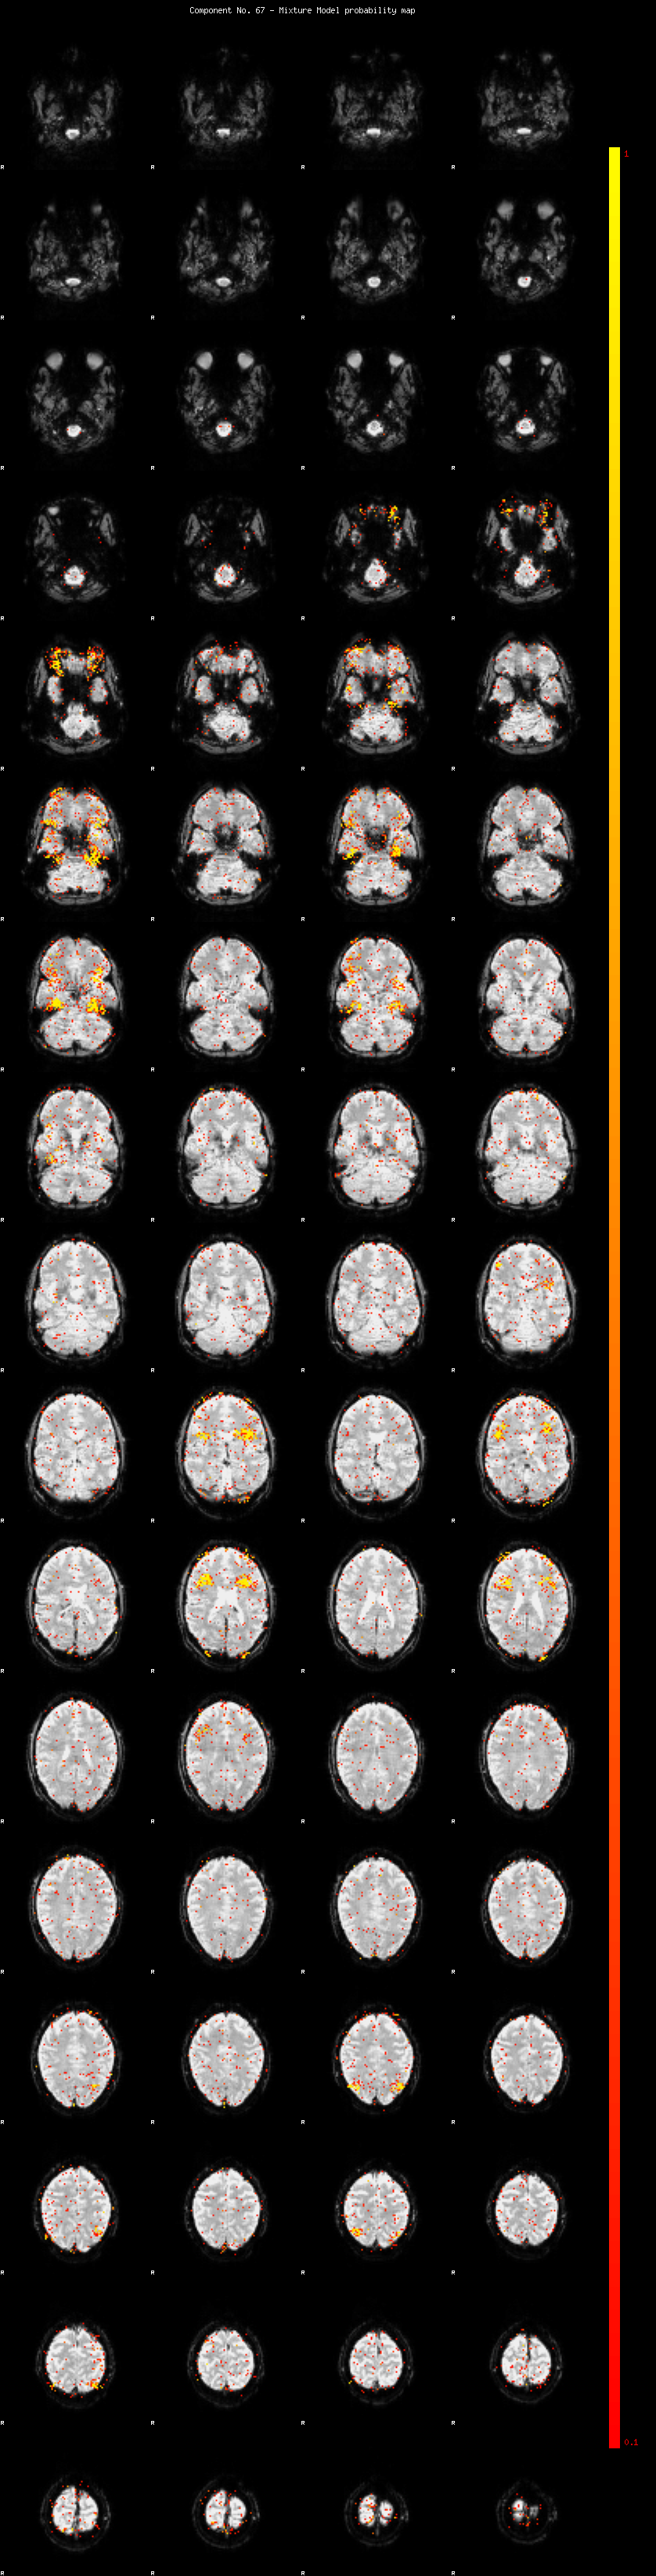

IC_67 Mixture Model fit

Means : 0.000000 2.467823 -2.721875

Vars : 1.000000 2.066205 2.965601

Prop. : 0.969186 0.015557 0.015258